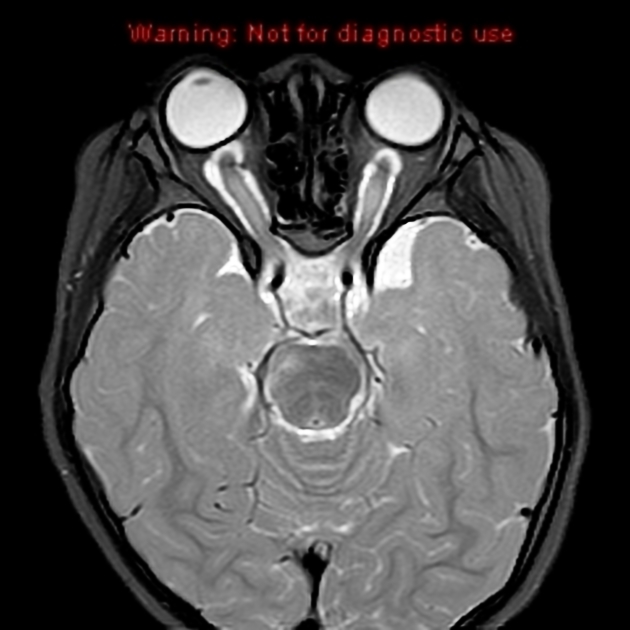

病理结果

视神经通路胶质瘤

图 8 两例视神经胶质瘤影像学表现:a 和 b 为一例,双侧视神经肿胀,可见强化改变,累及视交叉;c 和 d 为另一例,可见左侧视神经迂曲改变,结果证实为视神经胶质瘤

视神经胶质瘤是发生于视神经内胶质细胞的良性肿瘤,可沿视神经向颅内蔓延,可见于球后视神经、视交叉、下丘脑、视束至外侧膝状体通路上的任何部位。该病好发于 10 岁以内儿童,部分与神经纤维瘤病伴发,疑有遗传倾向。